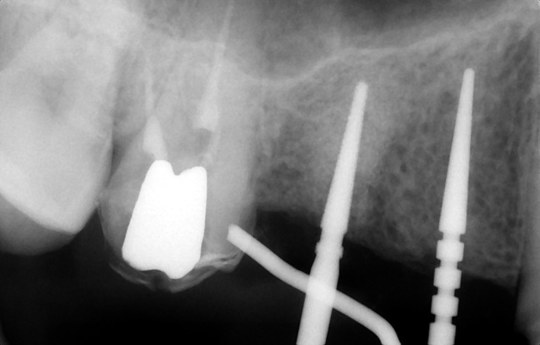

③埋入方向確認

歯科用CTとインプラントシミュレーションソフトによる事前の治療計画

また、事前検査にも負担軽減の工夫をしています。インプラントを埋め込むあごの骨には、重要な神経や血管があり、そこを誤って傷つけるようなことがあってはなりません。そのような危険性をできる限り少なくするためには、術前の精密な検査や診断が重要となります。そこでCTによる検査を行うことで、手術中の事故を防ぎ、より安全に治療を行えるよう努めているのです。